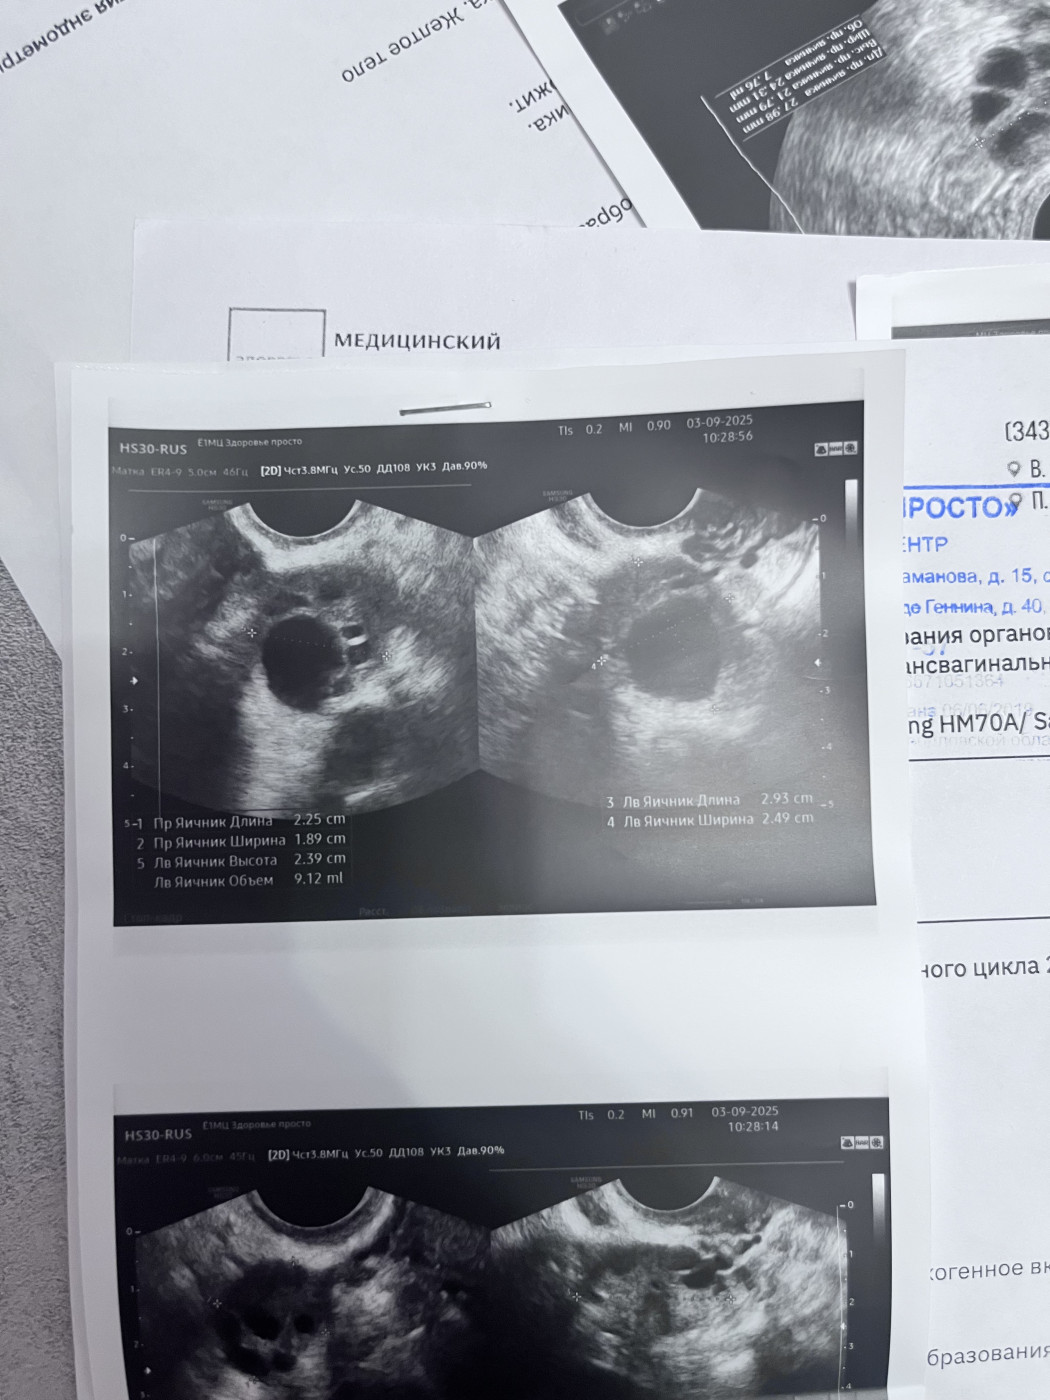

Результаты УЗИ

Киста, странные результаты повторного УЗИ